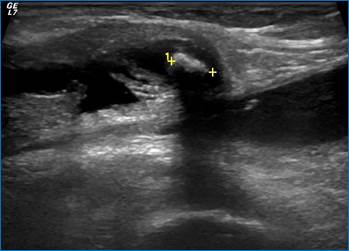

Частой случайной находкой может быть так называемая киста Бейкера (рис. 3), которая по сути представляет собой выпот в заднем завороте коленного сустава.

Рис. 3. Киста Бейкера